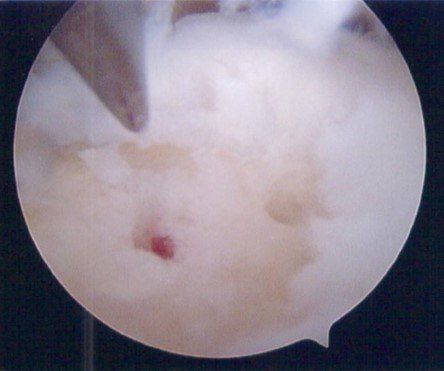

See X-ray and arthroscopic images below.

- ankle arthroscopy.

Surgery involves ankle arthroscopy and cartilage treatment. Depending on the size and depth of cartilage damage, options include:

- cartilage debridement and micro-fracture (+/- application of hydrogel bioscaffold) to stimulate healing (see images below)